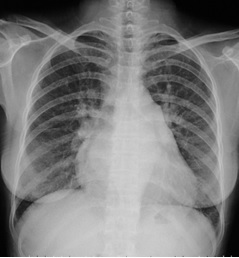

試題:根據(jù)下圖請做出正確診斷

A.正常心臟

B.心肌病(普大心)

C.風濕性心臟病(梨型心)

D.主動脈型心(靴型心)